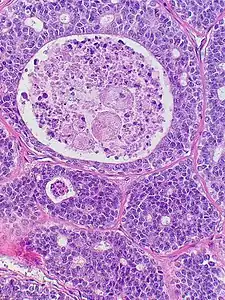

Histopathological image of adenoid cystic carcinoma of the salivary gland infiltrating a nerve (center), H&E stain